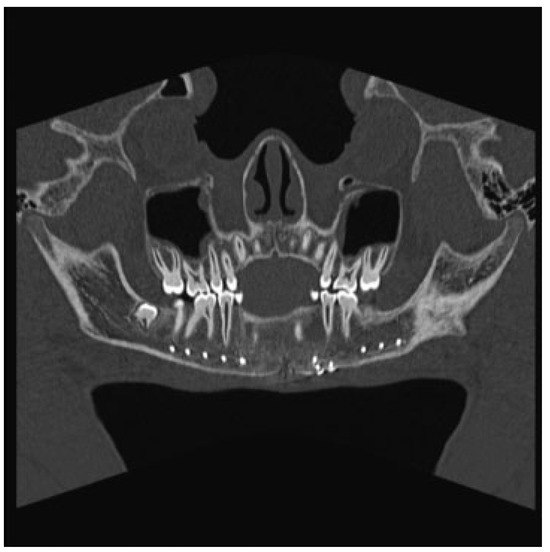

The patient was taken to the operating room the next day. With evidence of a lesion in the mandible of unknown pathology, the decision was made to proceed with a trans- cervical approach to provide broader access that would allow for adequate curettage and resection if needed. The fracture line and cystic cavity were identified. A cystic lumen was filled with organized blood clotlike material. No definitive solid tissue was identified (Figure 2). The clot and the cortex of the cavity were curetted and sent for histologic interpreta- tion. Occlusion had been established previously with max-illomandibular fixation. The mandibular fracture was reduced and repaired with a lower-border Synthes Matrix mandibular locking bar with bicortical screws (Synthes CMF, West Chester, PA, USA). An additional 2.0 Synthes Matrix mono- cortical plate was used to secure a sizable secondary fragment of the cystic wall (Figure 3). The cystic space was packed with Gelfoam (Pfizer, Pharmacia and Upjohn Company, Kalamazoo, MI, USA), as a means of filling the cystic dead space with a nonpermanent material that would not interfere with later osteogenesis. The remainder of surgery was uncomplicated and a small suction drain was placed at closing. A postoperative image revealed satisfactory alignment (Figure 4). The drain was removed on postoperative day 2, and the patient was dis-charged home 3 days later, tolerating a soft diet. Fifteen days after discharge, the patient returned to our ED with worsening pain and swelling at the surgical site. He was diagnosed with a small submental abscess. The patient was admitted and treated successfully with bedside incision and drainage and a short course of intravenous antibiotics. The remainder of his recovery was uneventful, with good occlusion and function. Follow-up CT imaging at 6 weeks showed good fracture healing and some early osteogenesis within the cystic cavity (Figure 5). One year after surgery, he had normal occlusion and no evidence of hardware complications. Additionally, CT imaging demonstrated ossification of the majority of the cystic space, with only a few small lateral areas of persistent cyst (Figure 6).

Figure 4.

Panorex computed tomography scan obtained in the immediate postoperative period showing improved anatomic alignment.